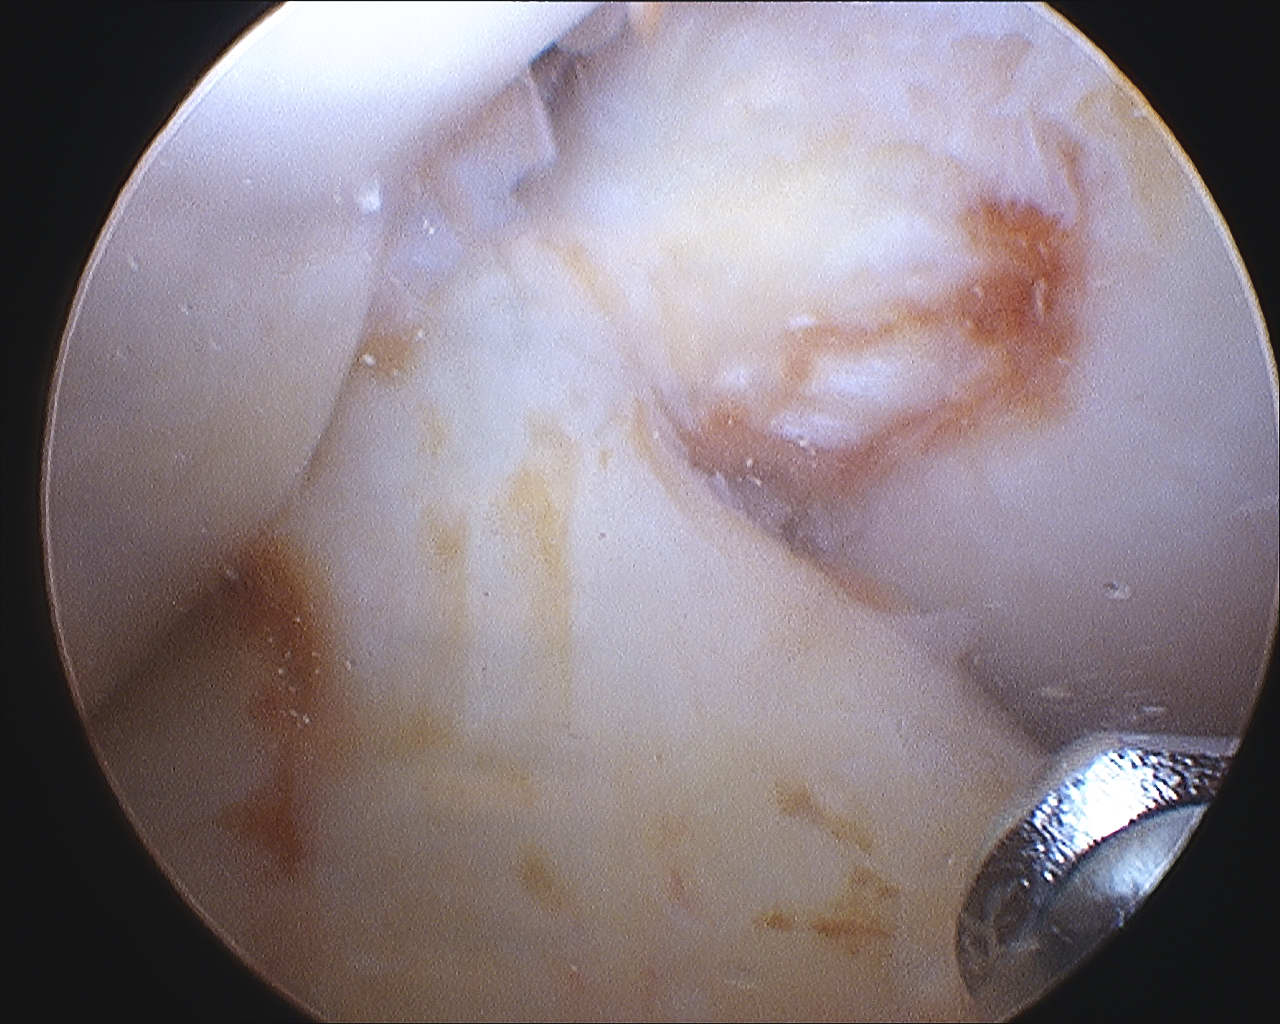

Localized / nodular PVNS anterior knee joint

Localized / nodular PVNS posteromedial compartment knee

Diffuse knee joint